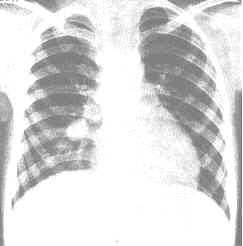

各種原因引起的胸部外傷因其衝力自胸壁向肺內傳導產生肺挫裂傷,造成肺泡或肺間質毛細血管充血、水腫、通透性增高,血管擴張甚至破裂出血,使血液漏至肺泡及肺間質。當胸部創傷的衝力向肺內傳導產生一種壓力時,使患者聲門緊閉,肺內壓力升高,肺組織發生撕裂,血液及氣體溢入其裂隙內,因周圍肺組織的彈力回縮作用形成束狀影,稱之為創傷性肺束腫。束記憶體有血液時可有液平面。如被血液填滿,稱為肺血腫。

主要是肺出血,由於肺血液循環豐富,損傷易出血,量可很多。加之血液的凝縮而成血腫,肺撕裂傷或肺血腫早期可僅顯示大片實變影,似肺挫傷,待後才出現創傷性肺束腫或肺血腫的典型X線徵象,這是因為在早期肺撕裂傷或肺血腫周圍被滲出性陰影掩蓋所致。